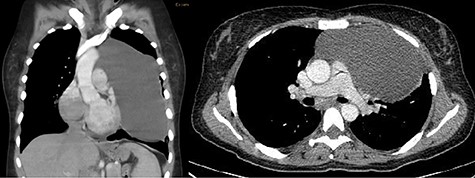

A 40-year-old female patient with a history of hypothyroidism was presented to the hospital with 5-day long flu-like symptoms (malaise, rhinorrhea and chills) along with cough and fever. By the time of her admission, she presented with dyspnea and an oxygen saturation level of 85%. On examination, the temperature was 37°C, respiratory rate 24 cycles/min, pulse rate 98 bpm, blood pressure 105/60 mm Hg. Rales were present at both pulmonary bases and mild abdominal pain was found on palpation over the upper right quadrant without peritoneal irritation signs. A chest x-ray was performed showing a radiopaque image at the left side of the cardiac silhouette from the second and seventh costal arc, deviation of the airway to the right side, and absence of pleural effusion (Fig. 1). A CT scan revealed a heterogeneous extrapulmonary multiloculated and predominantly fluid density lesion. It was located at the anterior mediastinum with left lateral extension. On intravenous contrast administration, wall enhancement of the lesion was observed, without pericardium involvement (Fig. 2).

(A) Coronal venous phase tomography showing a heterogeneous extrapulmonary multiloculated and predominantly fluid density tumor located in the left side lateral to the mediastinum with wall enhancement of the borders and no pericardium involvement. (B) Axial delayed phase tomography showing invasion of the tumor to the right thorax.